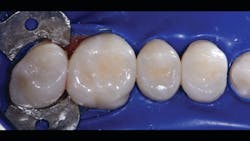

In the following case study (figures 1–11), the techniques and methods discussed will be demonstrated with the treatment of a quadrant of four posterior restorations. Four interproximal smooth-surface carious lesions are conservatively treated with two nonretentive saucer preparations and two marginal ridge-preserving opportunistic preparations.